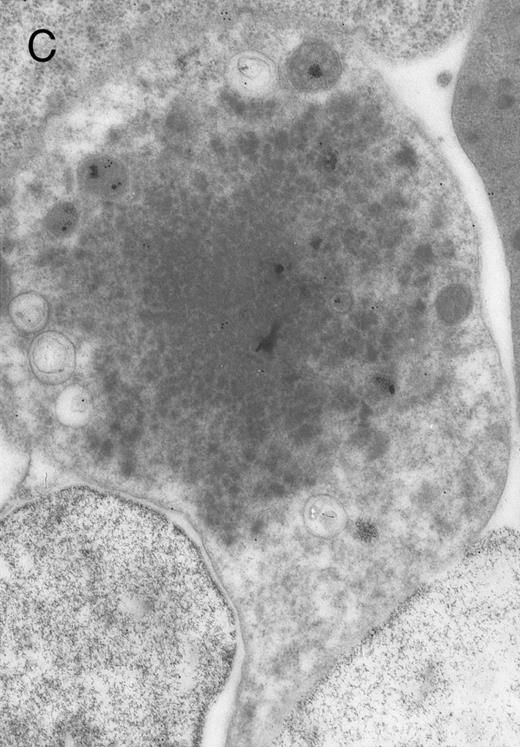

In both cases no. 1 and no. 2, electron microscope studies demonstrated electron-dense inclusions in 30% of early and late polychromatic erythroblast sections and many marrow reticulocytes. In ultrathin sections that reacted with monoclonal antibodies to either α- or β-globin chains followed by gold-labeled anti-mouse IgG, the density of gold particles over the majority of the inclusions was clearly greater than that over surrounding inclusion-free cytoplasm (Fig 3). By contrast, in sections from the two patients with β-thalassemia major, gold particles were concentrated over the inclusions following incubation with the antibody to α-globin chains, but not to β-globin chains (Fig 4A-C). The density of gold particles over inclusions in all control preparations was not greater than that over surrounding cytoplasm (Fig 4D).

Electron micrographs of erythroblastic inclusions from sections of marrow immunogold-labeled with mouse monoclonal antibody. Inclusions from a case of β-thalassemia major show a positive reaction with antibody against human α-globin chains (A, B) and no reaction with antibody against human β-globin chains (C). B shows part of the inclusion in A at higher magnification. There is virtually no labeling of inclusions in a control section that was reacted with normal mouse serum instead of a monoclonal antibody (D). Magnifications: A, × 20,000; B, × 59,000; C, × 23,000; D, × 35,000.

Prominent intra-erythroblastic inclusions were also present in both of these individuals (patients no. 1 and 2) with dominantly inherited β thalassemia. The percentage of polychromatic erythroblast sections containing inclusions in the two cases was 30%, which is considerably above the range (0.2% to 2.8%) previously reported in β-thalassemia trait.13 We have investigated the composition of the inclusions in cases no. 1 and 2 by immunoelectron microscopy using mouse monoclonal antibodies against human α- and β-globin chains and the immunogold technique. The intra-erythroblastic inclusions in the two cases reacted with both monoclonal antibodies to α- and β-globin chains, clearly indicating that these inclusions contained both types of chains. In contrast, the intra-erythroblastic inclusions found in homozygous β thalassemia reacted with the monoclonal antibody against α globin but not β-globin chains, confirming that they consisted only of precipitated α-globin chains. These data support the hypothesis that the cellular pathology underlying the dominantly inherited β thalassemias is related to the synthesis of highly unstable β-globin chains, which are not able to form functional tetramers. These abnormal β-chain variants precipitate intracellularly together with the concomitant excess α-globin chains to form large inclusions, which leads to more severe ineffective erythropoiesis than in heterozygous β thalassemia, in which much smaller amounts of precipitated globin chains are found.17